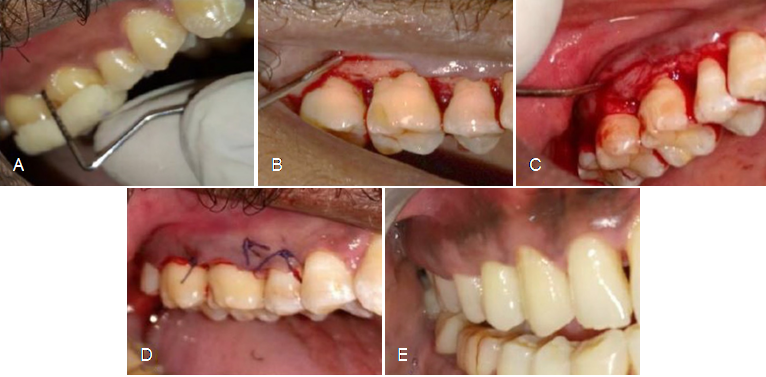

Figure 1 Surgical protocol of PRF Group A) Pre-operative image of surgical site in relation to 15,16,17 B) Simplified Papilla Preservation Flap performed in relation to 15,16,17 C) Platelet Rich Fibrin placement done in relation to 15,16,17 D) Internal Vertical mattress suturing done in relation to 15,16,17 E) Post-operative image after six months.

Figure 2 Surgical protocol of LLLT group A) Pre-operative image of surgical site in relation to 44,45,46 B) Simplified Papilla Preservation Flap performed in relation to 44,45,46 C) Low Level Laser Therapy stimulation done in 44,45,46 D) Internal Vertical mattress suturing done in 44,45,46 E) Post-operative image after six months.